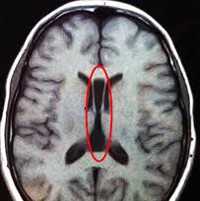

Наилучшими способами объективного выявления опухоли полушарий мозга признаны методы нейровизуализации: КТ и МРТ головного мозга. Они позволяют определить точную локализацию опухоли полушарий мозга и дифференцировать ее от внутримозговой гематомы, кисты при сирингомиелии, абсцесса головного мозга, рассеянного склероза, эпилепсии. Однако поставить достоверный диагноз и верифицировать опухоли полушарий мозга позволяет лишь гистологическое исследование. Оно может проводится с образцами мозговой ткани, полученными в ходе стереотаксической биопсии или интраоперационно.

- МРТ головного мозга. Магнитно-резонансная томография не оказывает лишней лучевой нагрузки на детский организм и позволяет более точно оценить объективные симптомы. МРТ рекомендована при глиомах, которые не накапливают контрастное вещество, поэтому плохо визуализируются на снимках КТ.